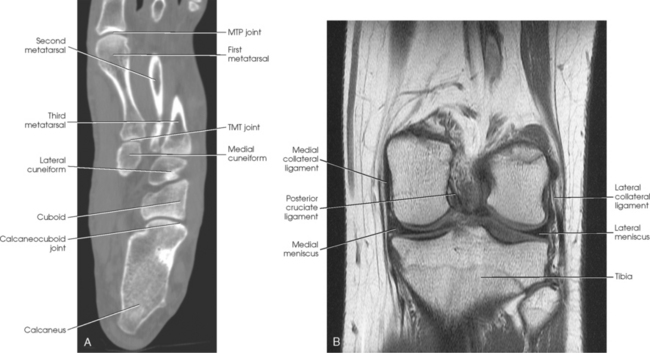

The joints of the lower limb are summarized in Table 6-1 and shown in Figs. 6-11 and 6-12. Beginning with the distalmost portion of the lower limb, the articulations are as follows.

Fig. 6-11 A, Axial CT scan of foot and calcaneus. B, MRI coronal plane of knee joint. Joint spaces are clearly shown.

Fig. 6-12 A and B, Joints of right foot. C, MRI sagittal plane of anterior foot. D, MRI sagittal plane of posterior foot and ankle. Joint spaces and articular surfaces are clearly shown.

The interphalangeal (IP) articulations, between the phalanges, are synovial hinges that allow only flexion and extension. The joints between the distal and middle phalanges are the distal interphalangeal (DIP) joints. Articulations between the middle and proximal phalanges are the proximal interphalangeal (PIP) joints. With only two phalanges in the great toe, the joint is known simply as the IP joint.

The distal heads of the metatarsals articulate with the proximal ends of the phalanges at the metatarsophalangeal (MTP) articulations to form synovial ellipsoidal joints, which have movements of flexion, extension, and slight adduction and abduction. The proximal bases of the metatarsals articulate with one another (intermetatarsal articulations) and with the tarsals (tarsometatarsal [TMT] articulations) to form synovial gliding joints, which permit flexion, extension, adduction, and abduction movements.

The intertarsal articulations allow only slight gliding movements between the bones and are classified as synovial gliding or synovial ball-and-socket joints (see Table 6-1). The joint spaces are narrow and obliquely situated. When the joint surfaces of these bones are in question, it is necessary to angle the x-ray tube or adjust the foot to place the joint spaces parallel with the central ray.

The calcaneus supports the talus and articulates with it by an irregularly shaped, three-faceted joint surface, forming the subtalar joint. This joint is classified as a synovial gliding joint. Anteriorly, the calcaneus articulates with the cuboid at the calcaneocuboid joint. This joint is a synovial gliding joint. The talus rests on top of the calcaneus (see Fig. 6-12). It articulates with the navicular bone anteriorly, supports the tibia above, and articulates with the malleoli of the tibia and fibula at its sides.